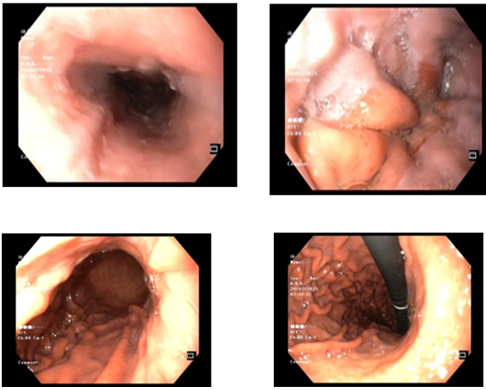

- Nội soi dạ dày, đại trực tràng: Giãn tĩnh mạch thực quản độ II – Viêm dạ dày – Viêm hành tá tràng. Nội soi đại tràng bình thường.

Hình 3.